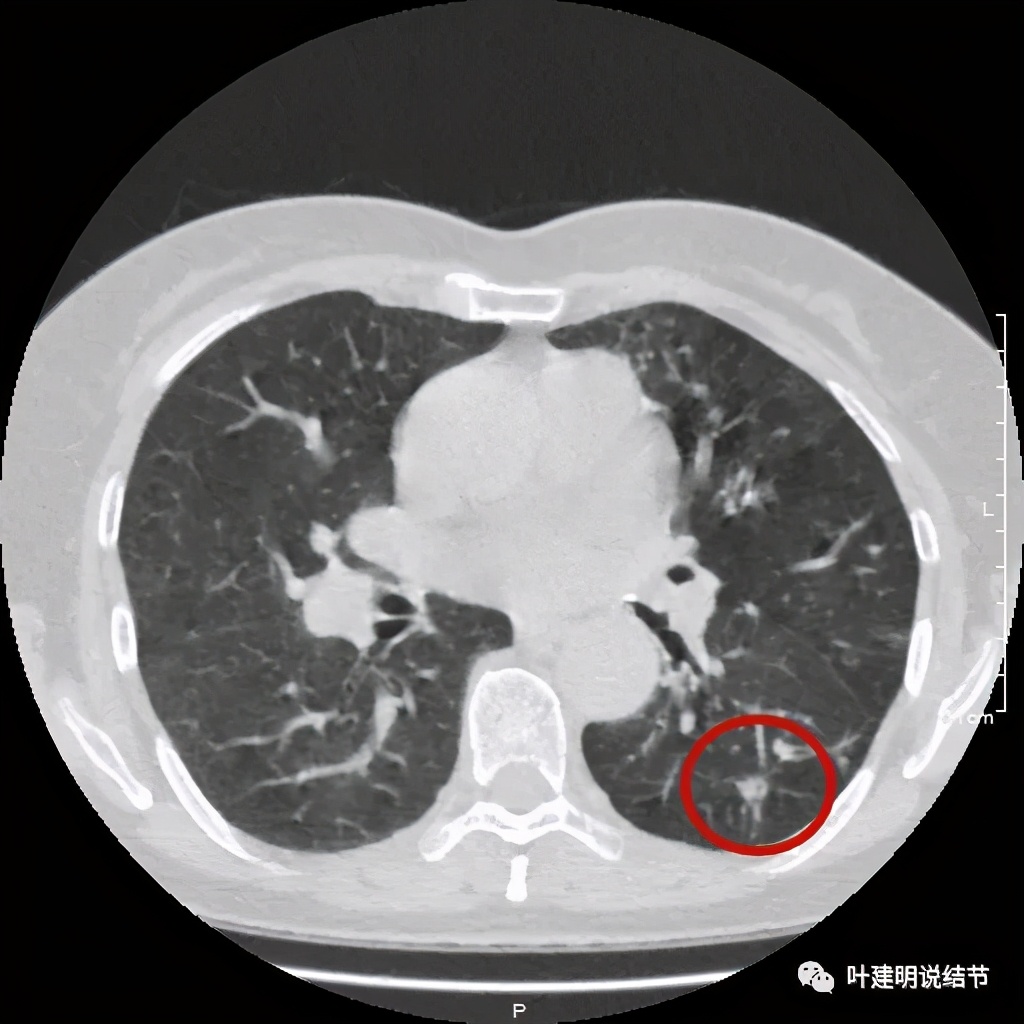

金华的某A,女性,56岁,去年8月份检查发现左肺下叶结节,是实性的,还中间有个空洞,我们说若磨玻璃结节伴空泡或空腔多为恶性范畴的,实性的也是可能性会大一些,但不如磨玻璃确切,因为结核、感染等也会类似的。我们先来看她当时的CT图像:

左下结节与血管关系密切,此层似磨玻璃结节,还夹在小血管之间,其中有血管紧贴病灶,略迂曲